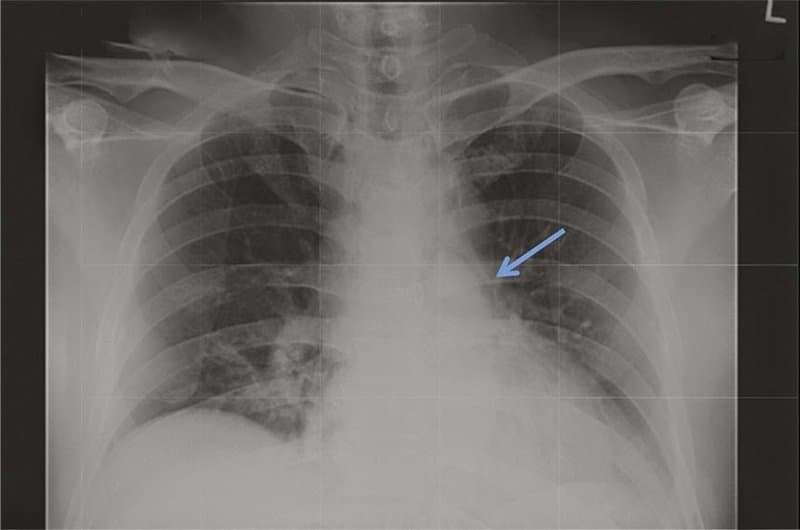

Sự hiện diện của không khí hoặc khí tự do trong trung thất được gọi là tràn khí trung thất. Tràn khí trung thất là một tình trạng lành tính và tự giới hạn, thường gây ảnh hưởng đến nam giới.

3. Dấu hiệu tràn khí trung thất

Tràn khí trung thất tự phát là bệnh lý lành tính, hiếm gặp và chủ yếu gặp ở người trẻ tuổi. Những biểu hiện lâm sàng hay gặp nhất là đau ngực, khó thở và tràn khí dưới da.

Bệnh nhân bị tràn khí trung thất có thể không có triệu chứng. Bệnh thường gây đau ngực sau xương ức, có thể lan tới cổ và cánh tay. Khi thở và nuốt có thể khiến cơn đau tăng lên.

Những triệu chứng thường gặp nhất là đau ngực, khó thở và cảm giác đau hoặc khó chịu ở cổ. Đau ngực là triệu chứng được thấy nhiều nhất và có đặc điểm là đau cấp tính, sau xương ức, kiểu màng phổi và có thể lan lên cổ, vai hoặc ra sau lưng. Một số triệu chứng ít gặp hơn gồm: Ho, nuốt khó, nuốt đau, đau lưng hoặc đau bụng.